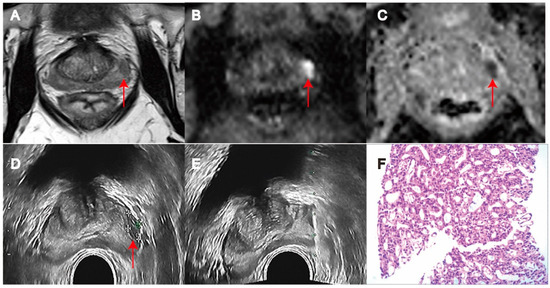

Comparison of Targeted Biopsy and Combined Biopsy to Avoid Unnecessary Systematic Biopsy in Patients with PI-RADS 5 Lesions

2. Materials and Methods

2.3. Prostate Biopsy